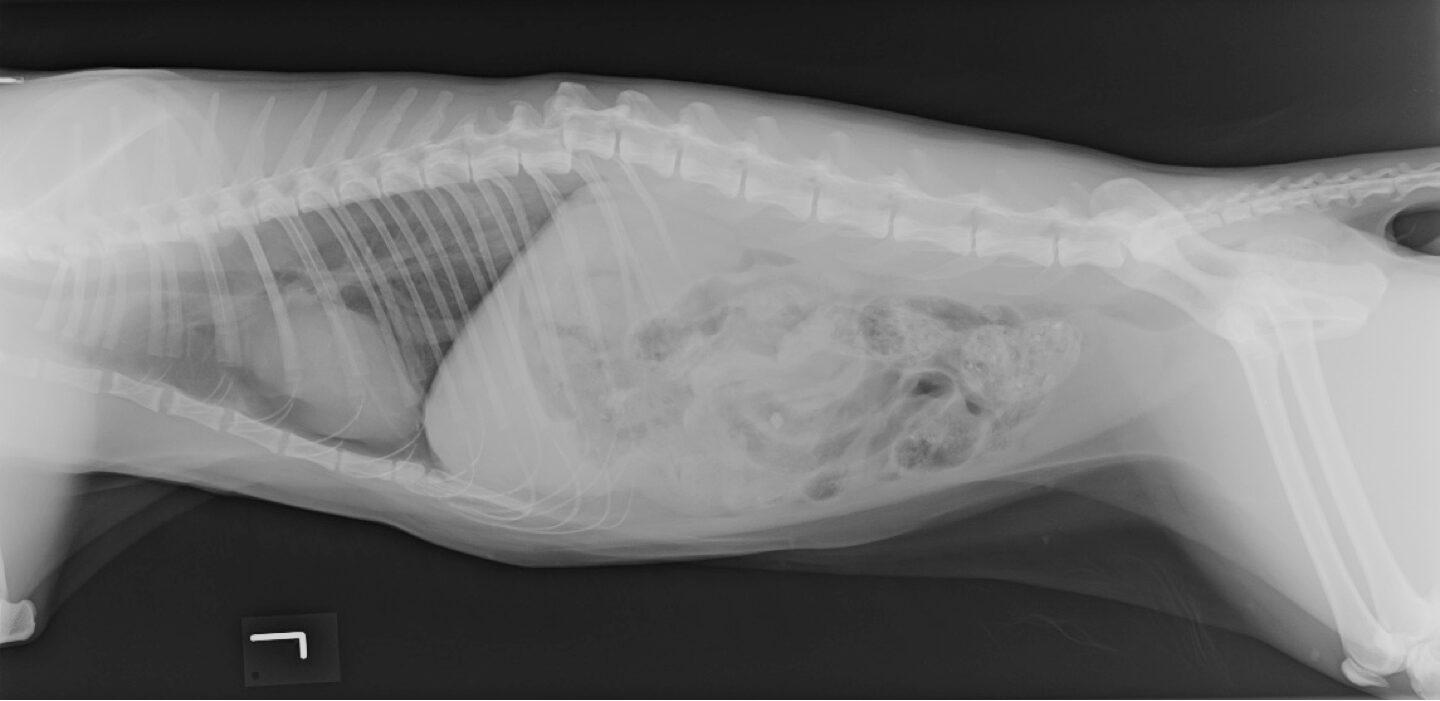

Orthopädische Notfälle bei der Katze

Orthopädische Fälle werden häufig als Notfälle vorgestellt, stellen aber aus orthopädischer Sicht selten Notfälle dar, die direkt chirurgisch versorgt werden müssen. Was auf den ersten Blick etwas verwirrend erscheint, soll im Folgenden anhand von verschiedenen Symptomen erläutert werden. Notfälle mit orthopädischen Problemen und deren Erstversorgung sind sehr wichtig, um ein gutes Outcome zu gewährleisten. Tatsächliche orthopädische Interve